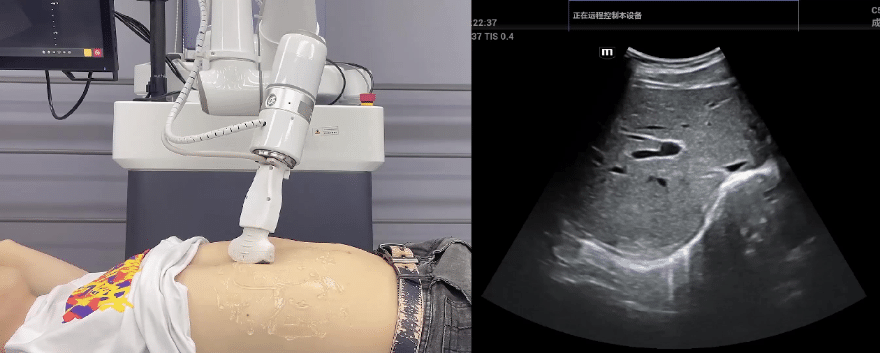

G22恒峰协作机器人与超声深度打通,最大程度保留医生左右手同时操作传统超声的习惯,并改善其舒适性,超声检查实际应用场景展示如下:

肝脏、胆囊、胰腺扫查